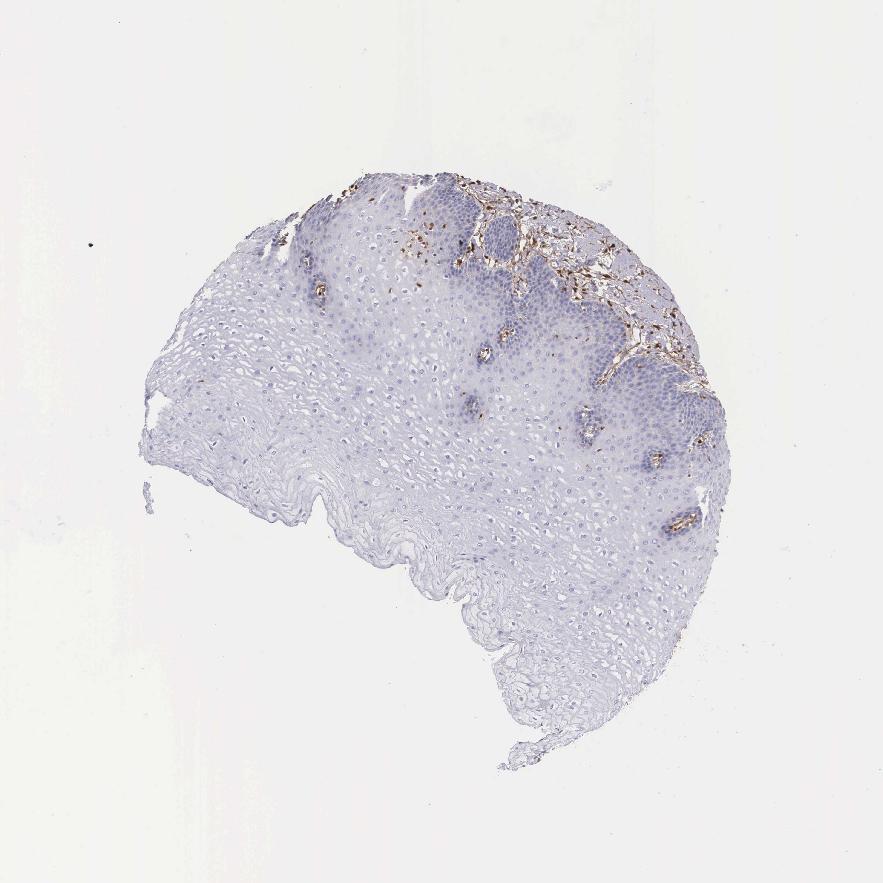

TISSUE PRIMARY DATA ESOPHAGUS Show tissue menu

ESOPHAGUS - Antibody stainingi

Antibody staining in the annotated cell types in the current human tissue is reported as not detected, low, medium, or high, based on conventional immunohistochemistry profiling in selected tissues. This score is based on the combination of the staining intensity and fraction of stained cells.

Each image is clickable and will lead to virtual microscopy that enables deeper exploration of all samples and also displays staining intensity scores, fraction scores and subcellular localization as well as patient and tissue information for each sample.

Antibody HPA000646Antibody CAB002157

Squamous epithelial cells Not detectedNot detected